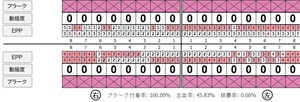

症例3

来院2回目、TBI後

SRP後

初診時、TBI前

| 年齢・性別 | 27歳・男性 |

|---|---|

| 主訴 | 主訴:左右下の歯ぐきに違和感がある 治療部位:全顎 |

| 治療内容 | 1.歯周基本検査、レントゲン撮影、口腔内写真、歯磨き指導、歯石除去、着色除去 2.SRP(スケーリングルートプレーニング)、再評価 その他 3.親知らずの抜歯 4.カリエス処置:右上1.2.3左上1.2.3右下6左下7CR(レジン充填)、右下7セラミックIn 5.定期検診 |

| 治療期間 | 6ヶ月 |

| 治療費 | ※歯周基本治療の費用:PMTC以外保険診療3割負担 合計:19,680円 1.初診検査(歯周ポケット検査.レントゲン撮影):3,010円 2.歯磨き指導、歯面の歯石除去:1,410円 3.PMTC(自由診療):5,500円 4.SRP(歯周ポケット内の歯石除去)×4回:約2,000円/回 5.再評価:1,760円 (2023年12月現在) |

| リスク・副作用 | ・最初は歯磨きをすると歯ぐきから出血するが毎日ホームケアを続けることで出血が徐々になくなる ・歯ぐきが腫れている状態が改善されると歯ぐきが引き締まり退縮するため、歯ぐきが下がったように感じることがある ・歯ぐきが引き締まると歯間が開いたように感じることがある ・歯ぐきが引き締まると知覚過敏の症状がでる可能性がある ・一度歯石を除去しても毎日のホームケアを怠ると再度歯石がつく ・治療後も再発を防ぐために定期的なメインテナンスが必要である |

| 治療方針 | 1.初診検査(レントゲン撮影、口腔内写真、歯周検査、歯磨き指導) 2.歯磨きチェック、歯石除去、PMTC 3.SRP 4.再評価 5.定期検診 |

| 特記事項 | ・歯科医院は今回初めて ・タバコは24歳まで3年ほど吸っていたが健康のためにやめた ・親知らずは右下以外抜歯 ・歯ブラシはルシェロP20M、補助用具はフロスを処方 |

| 担当者所見 | 全体的に歯と歯ぐきの境目に歯垢(細菌の塊)が残り、日々のホームケアで落とし切れていなかったことと、歯科医院への定期検診の習慣がなかったことから、全顎的な歯肉炎になってしまったと考えられる。 歯周基本治療とホームケアで歯ぐきの腫れや歯周ポケット、出血率などかなり改善されたが、出血がまだ0%ではない為、引き続き歯ブラシの当て方をお伝えしつつ今後は定期検診で3ヶ月おきに再発しないよう一緒に管理していく。 |